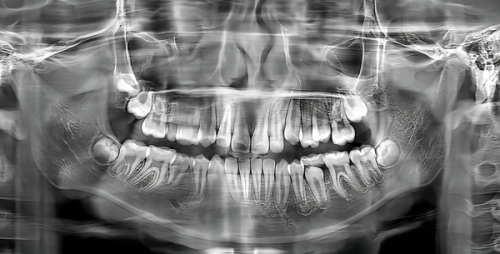

在日常生活中,特别多人都面临着各种各样的牙齿问题。有的人牙齿发黄、发黑,重度影响了个人形象,导致在社交场合中缺乏自信,不敢开怀大笑;有的人患有龋齿,牙疼起来要命,吃饭、睡觉都受到极大影响,生活质量直线下降;还有的人牙齿排列不整齐,不仅影响美观,还可能导致清洁不到位,引发更多口腔疾病。这些牙齿问题就像隐藏在我们生活中的“小恶魔”,时刻折磨着我们,让我们焦虑不已。

上海秋谨口腔诊所拥有一支专精的口腔医疗团队,他们都具备丰富的临床经验和专精知识,能够为患者提供个性化的治疗方案。对于牙齿美白问题,诊所采用精良的美白技术,能够在短时间内让你的牙齿变得洁白亮丽。针对龋齿,医生会根据病情进行科学的治疗,从根本上解决牙疼问题。而对于牙齿矫正,诊所引进了多种精良的矫正技术,如隐形矫正,让你在不知不觉中拥有整齐的牙齿。